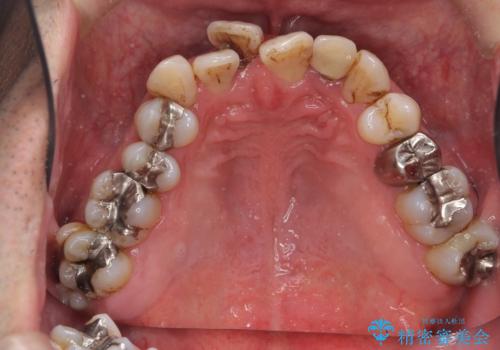

- 歯周病を気にして来院。

前歯の虫歯を治そうにも、歯並びの問題で難しい状態でした。

前歯が重なっているところの虫歯治療が難しく、そこから矯正治療の提案となりました。

下の前歯1本、また、左上2番を保存不可能なため抜歯しています。

通常骨格的な受け口を部分矯正でというのは不可能なことが多いのですが、今回はいろいろな条件が重ねなりお引き受け可能でした。通常は難しいです。